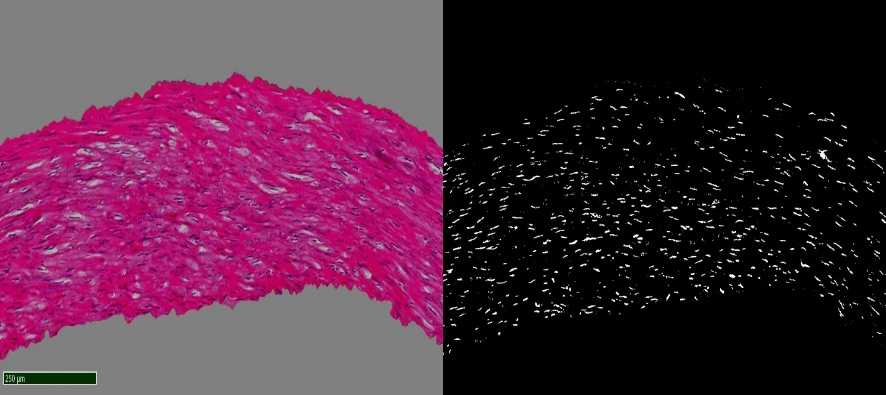

Histological examination was performed on days 7, 14, 21, 28, 35, 42, 49, 56, 63, 70, 77, 84 after homograft collection, ten arterial and ten venous preparations respectively. Twelve comparison groups of arterial and venous homografts were obtained. One hundred twenty arterial and 120 venous specimens were studied. The number of myocyte nuclei in the middle layer of homografts was estimated using automatic counting in the Image-PRO Plus 6.0 program (Figure 1) and recalculation of the obtained values per 0.01 mm2 (10,000 μm2) of the area of the middle layer of the vessel homograft wall. Counting was performed in 1 field of view at medium magnification (×100) using digital processing to visualize muscle cell nuclei. The software used was NDP.view2 (U12388-01; Hamamatsu Photonics KK).

Fig. 1. The stages of digital processing of the homograph wall (magnified ×100).